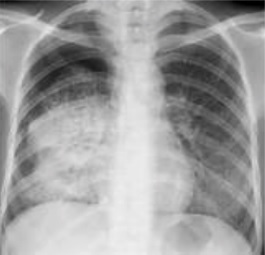

In active pulmonary TB, infiltrates or consolidations and/or cavities are often seen in the upper lungs with or without mediastinal or hilar lymphadenopathy.[1] However, lesions may appear anywhere in the lungs. In HIV and other immunosuppressed persons, any abnormality may indicate TB or the chest X-ray may even appear entirely normal.[1]

4. Pleural effusion - Presence of a significant amount of fluid within the pleural space. This finding must be distinguished from blunting of the costophrenic angle, which may or may not represent a small amount of fluid within the pleural space (except in children when even minor blunting must be considered a finding that can suggest active TB).

5. Hilar or mediastinal lymphadenopathy (bihilar lymphadenopathy) - Enlargement of lymph nodes in one or both hila or within the mediastinum, with or without associated atelectasis or consolidation.